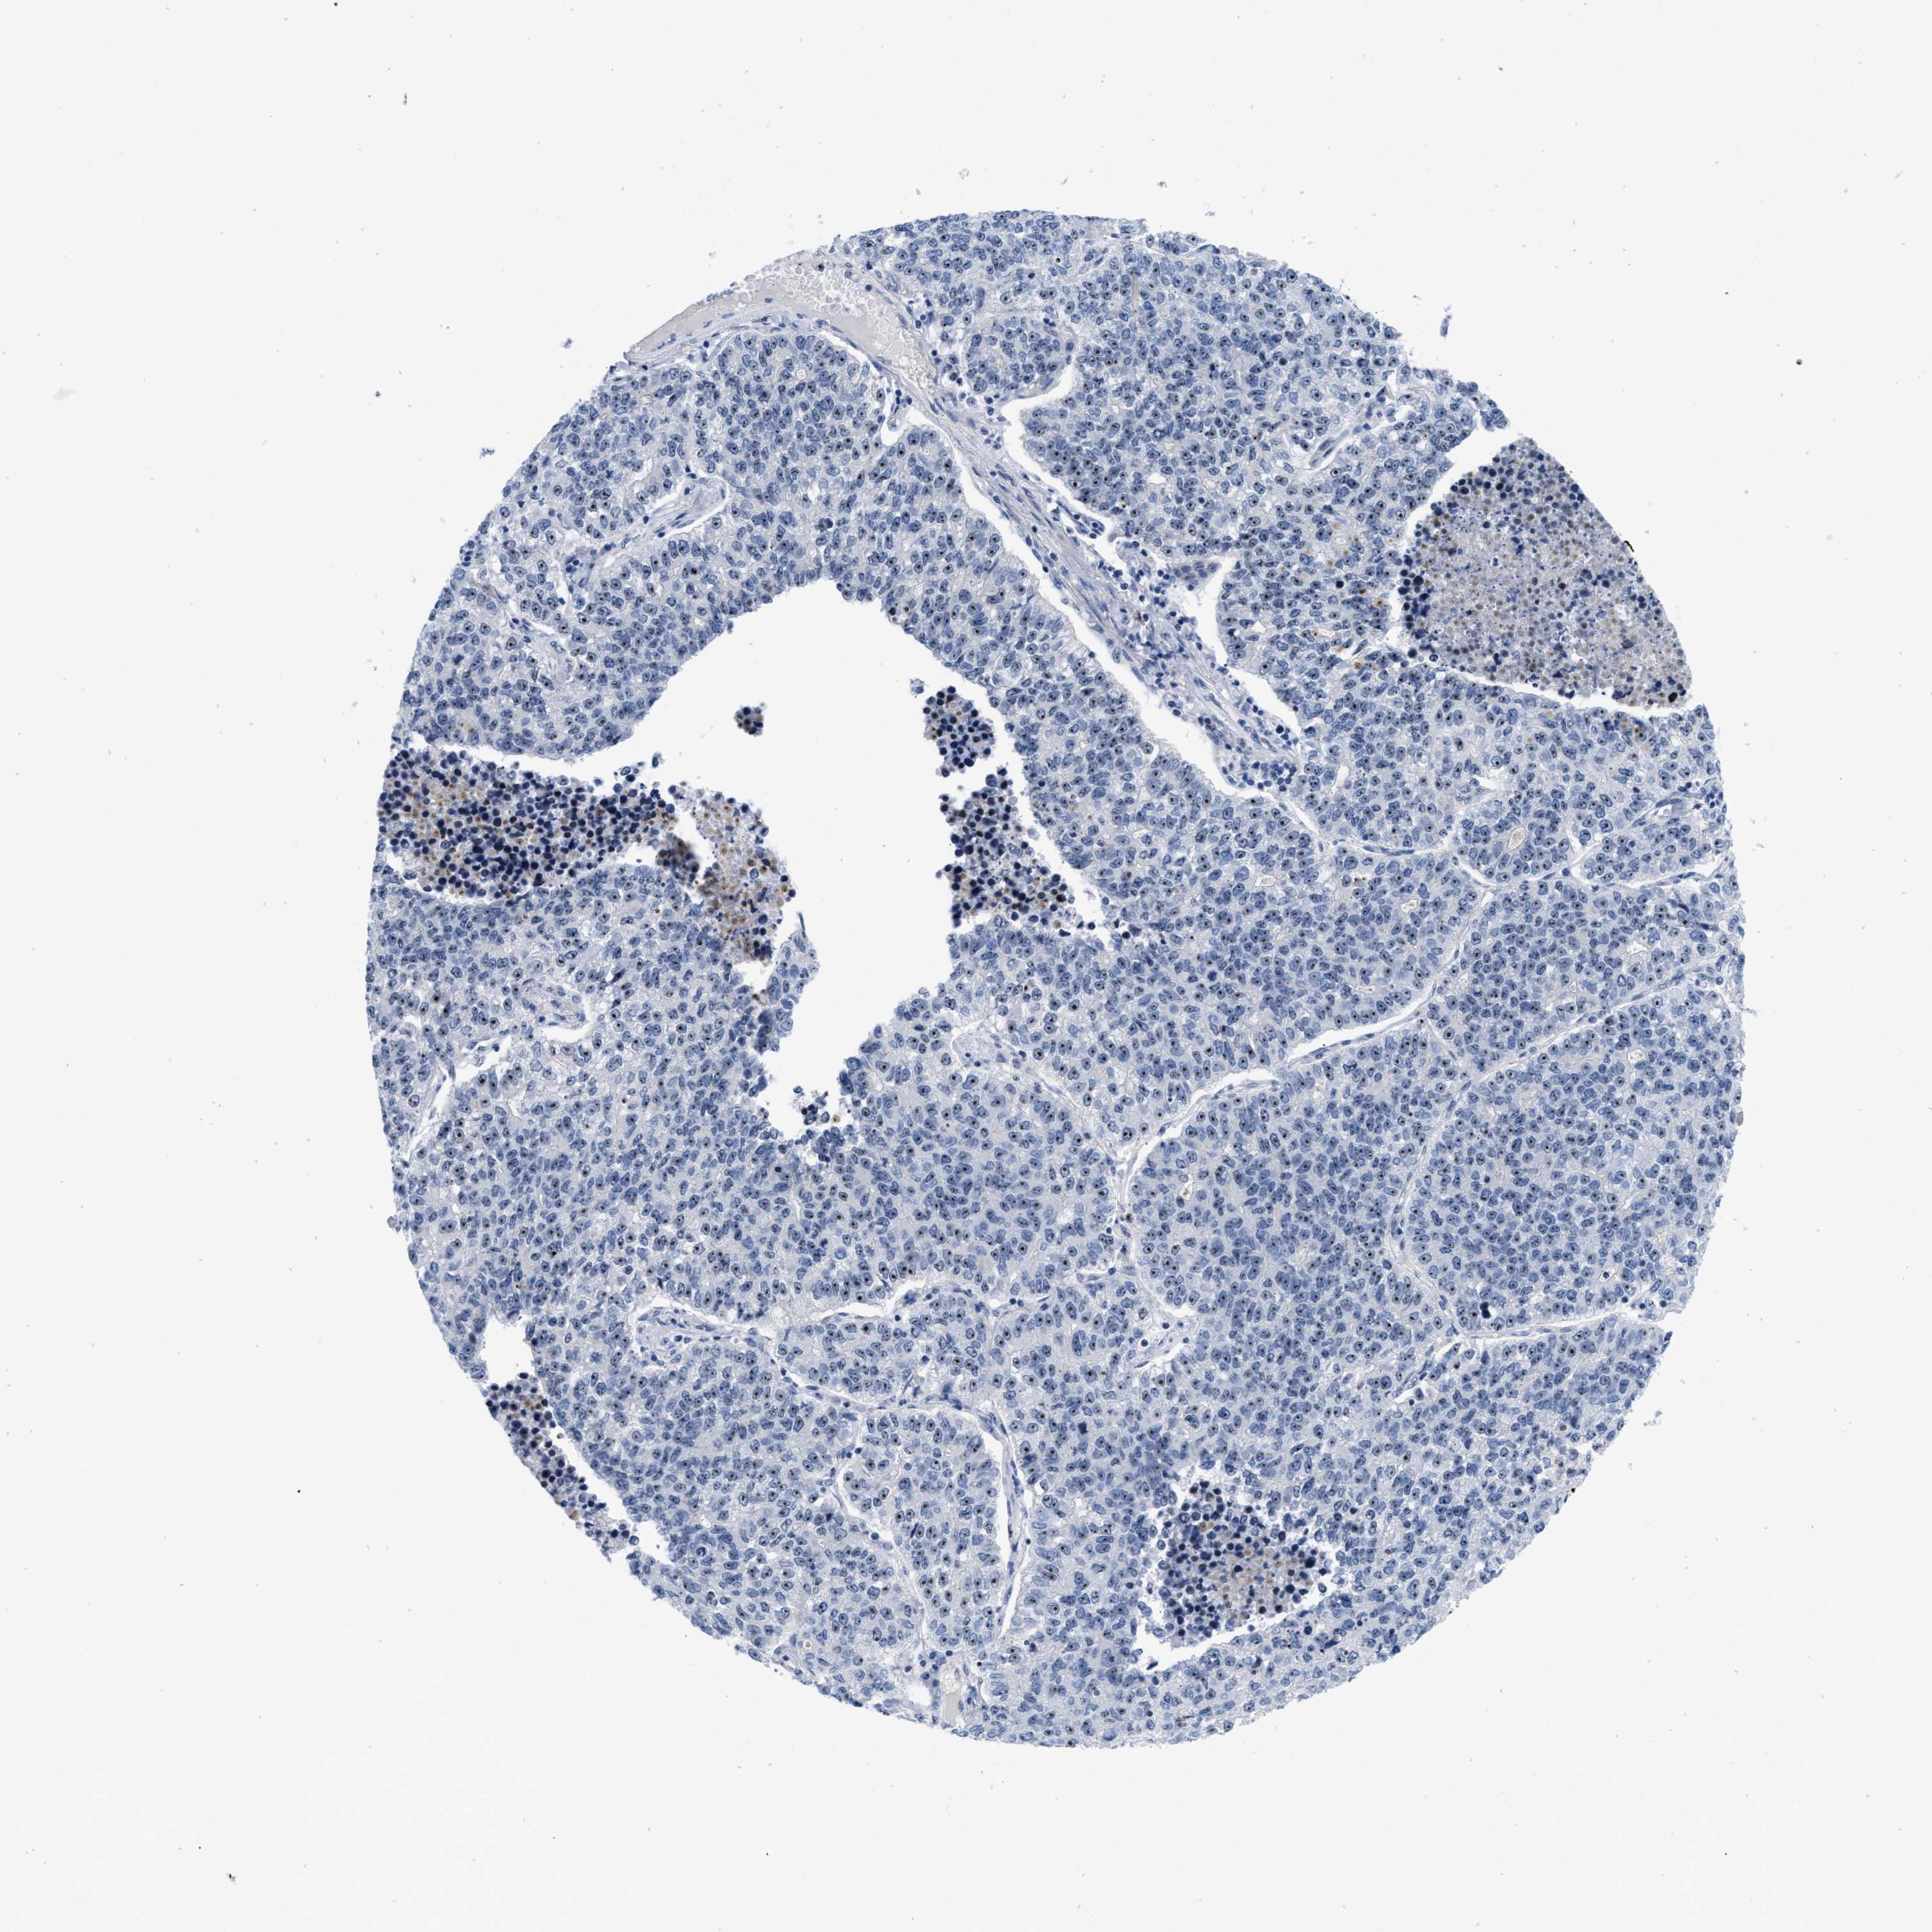

CANCER LUNG CANCER Show tissue menu

LUAD TCGA LUAD VALIDATION LUSC TCGA LUSC VALIDATION PROTEIN LUAD CPTAC PROTEIN LUSC CPTAC PROTEIN EXPRESSION